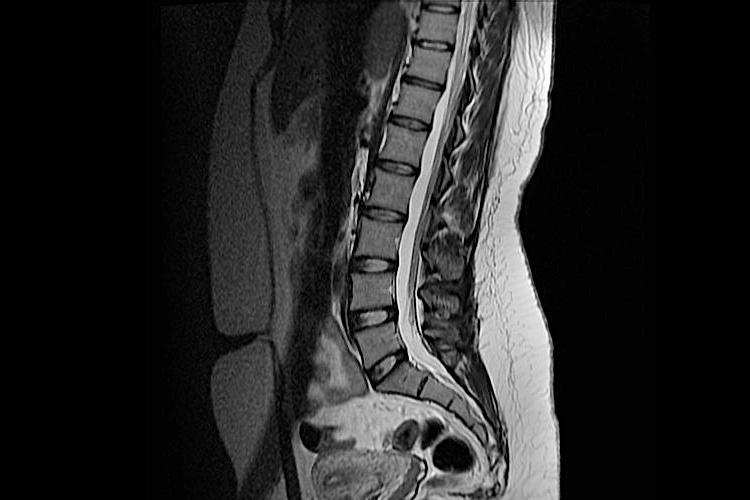

• рентгенография крестца и копчика;

• КТ/МРТ органов брюшной полости и малого таза;